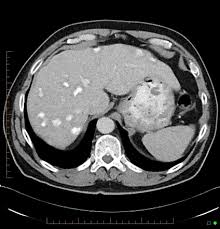

Development Of An Orthotopic Model Of Human Metastatic Prostate Cancer In The Nod Scidg Mouse Mus Musculus Anterior Prostate

Development Of An Orthotopic Model Of Human Metastatic Prostate Cancer In The Nod Scidg Mouse Mus Musculus Anterior Prostate from www.spandidos-publications.com